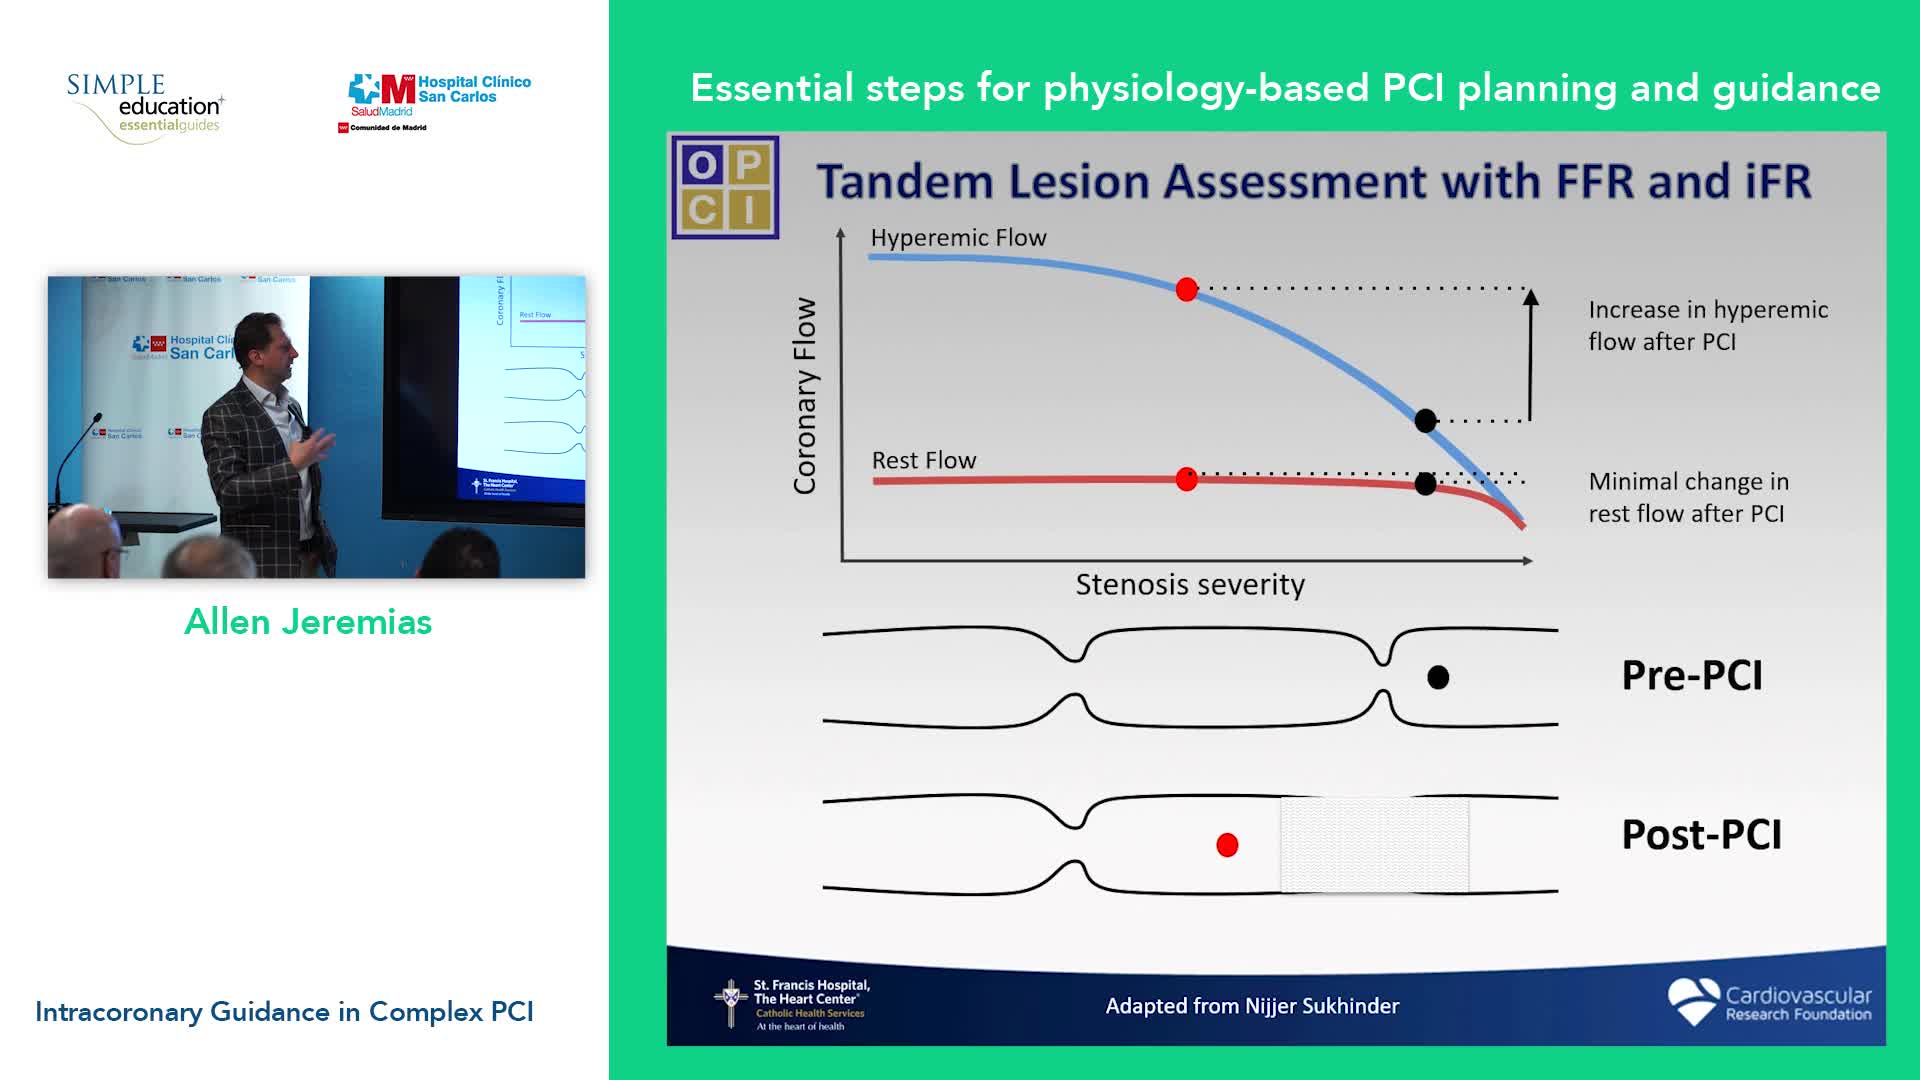

Essential steps for physiology-based PCI planning and guidance - Dr Allen Jeremias